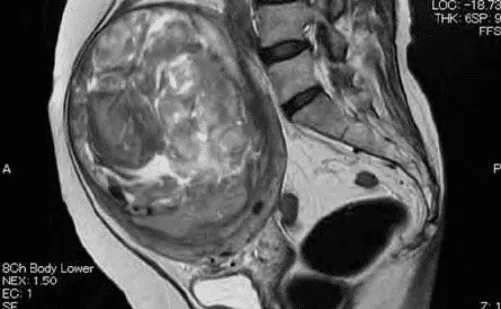

MRI: Phân biệt adenomyosis (JZ dày > 40%, tín hiệu hỗn hợp) với u xơ (tín hiệu đồng nhất giảm trên T2W).

Hình ảnh “MRI của adenomyosis và u xơ tử cung”.

Hình ảnh “Leiomyosarcoma trên MRI”.